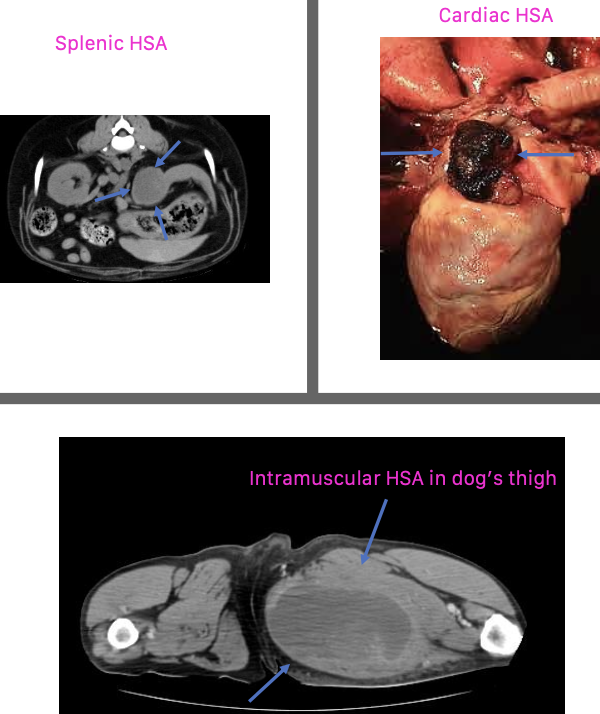

what are common locations of primary hemangiosarcoma?

can occur anywhere:

1. visceral

2. cardiac

3. dermal/SQ/intramuscular

what are the common primary visceral sites of hemangiosarcoma?

-spleen is the most common location

-liver

-other: kidney, retroperitoneal space, nasal cavity, oral cavity, bone

what are the common primary cardiac sites of hemangiosarcoma?

second most common primary site:

-right atrium

-right auricle

what is the appearance of hemangiosarcoma lesions in the abdomen using abdominal ultrasound?

-heterogenous (hypoechoic to targetoid to mixed)

-cavitation

- +/- peritoneal effusion